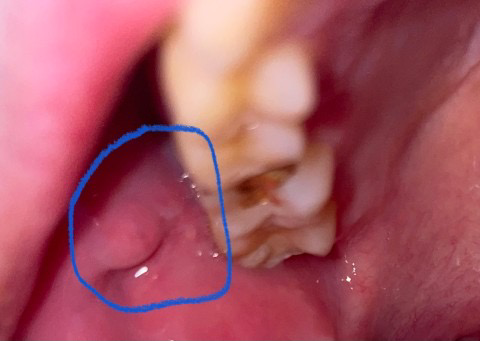

네 맞습니다. 대타액선 중 하나인 이하선이며 이하선의 개구부가 맞습니다. 해당 부위로 침이 나오는 곳입니다. 사람에 따라서 그 크기가 다를 수 있으며 남들 보다 클 수도 있습니다. 별다른 통증이나 불편감이 없다면 걱정 안해도 됩니다.

이하선 개구부 입니다. 이비인후과 진료를 보는것이 좋을것 같습니다.

저부분은 이하선 개구부라기 보다는 볼살이 치아에 씹혀서 생겻을 가능성이 높습니다. 크게 문제가 잇는건 아니니 너무 걱정하지 마세요.